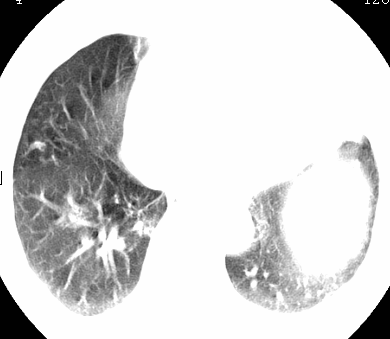

标题: CT26680:肺部右下肺静脉干结节的界定 [打印本页]

标题: CT26680:肺部右下肺静脉干结节的界定

经追查说有支扩咯血病史,但不确定

考虑1、周围型肺癌,2肺静脉畸形,前者可能大,建议增强检查。

考虑1、周围型肺癌,2肺静脉畸形,前者可能大,建议增强检查。支持!

不排除右肺下叶周围型肺癌可能。

中心型肺癌,纤支镜可帮助明确。